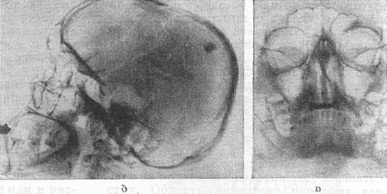

При рентгенодіагностиці захворювань черепа необхідно поряд з глибокими знаннями основ рентгеноанатомии враховувати його вікові, статеві та конституціональні особливості, а також анатомічні варіанти та аномалії розвитку кісткових елементів і черепних швів: інтернейрони - вормиевы - кістки, черепицеобразное розташування луски кісток у ламбдовидном шві (рис. 11,6) ділянки стоншування кісток склепіння (foramina parietalia permagna), пневматизация крил основної кістки та ін. Це необхідно, з одного боку, для того, щоб уникнути гипердиагностических висновків, а з іншого,- не переглянути початкові патологічні зміни в тих випадках, де вони насправді є.

Вивчення їх стану нерідко вимагає застосування спеціальних двухмоментных проекцій для зіставлення однойменних деталей правої і лівої сторін. Іноді незначна деструкція або відносно невелике розширення одного з каналів може вказувати на наявність пухлини відповідного нерва (див. Головний мозок, рентгенодіагностика захворювань). Так, наприклад, при глиоме зорового нерва обов'язково дослідження в проекції Резе - Голвина (рис. 4), а при невриномі VIII нерва, розширює внутрішній слуховий прохід,- проекції пірамід по Стенверсу (рис. 14).